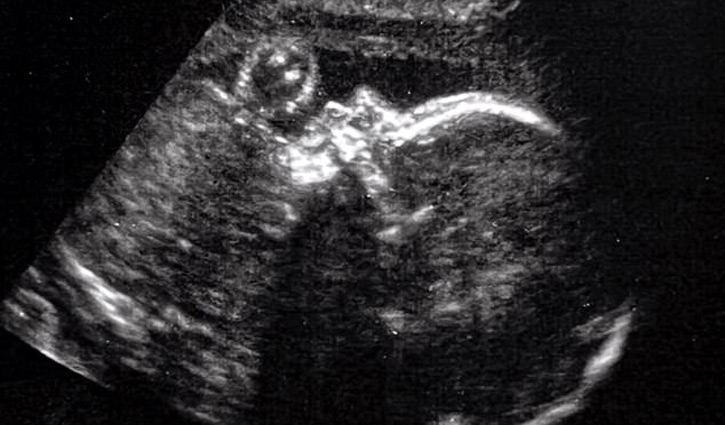

The operation, performed by doctors in Boston, was performed by slicing into the pregnant woman's abdomen and using an ultrasound to identify the artery and guide the surgery.

Then, using ultrasound to pinpoint the correct spot, they cut into her uterine wall.

Surgeons then proceeded to slice into the unborn child's brain and perform surgery to implant a coil near the artery that would restrict blood flow.